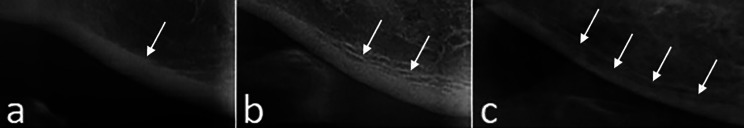

C1 (Normal Mandibular Cortex): The margins are equal and sharp on both sides of the cortex (Fig. 3a).

C2 (Moderately Resorbed Mandibular Cortex): The endosteal margins of the cortex show half-moon-shaped defects (lacunar resorption) and the margins are observed as 1–3 layers (Fig. 3b).

C3 (Severely Resorbed Cortex): Cortical cortices are severely porous and dense endosteal debris is present (Fig. 3c).

Fig. 3.

MCI description on cropped panoramic images (a:C1, b:C2, c:C3)